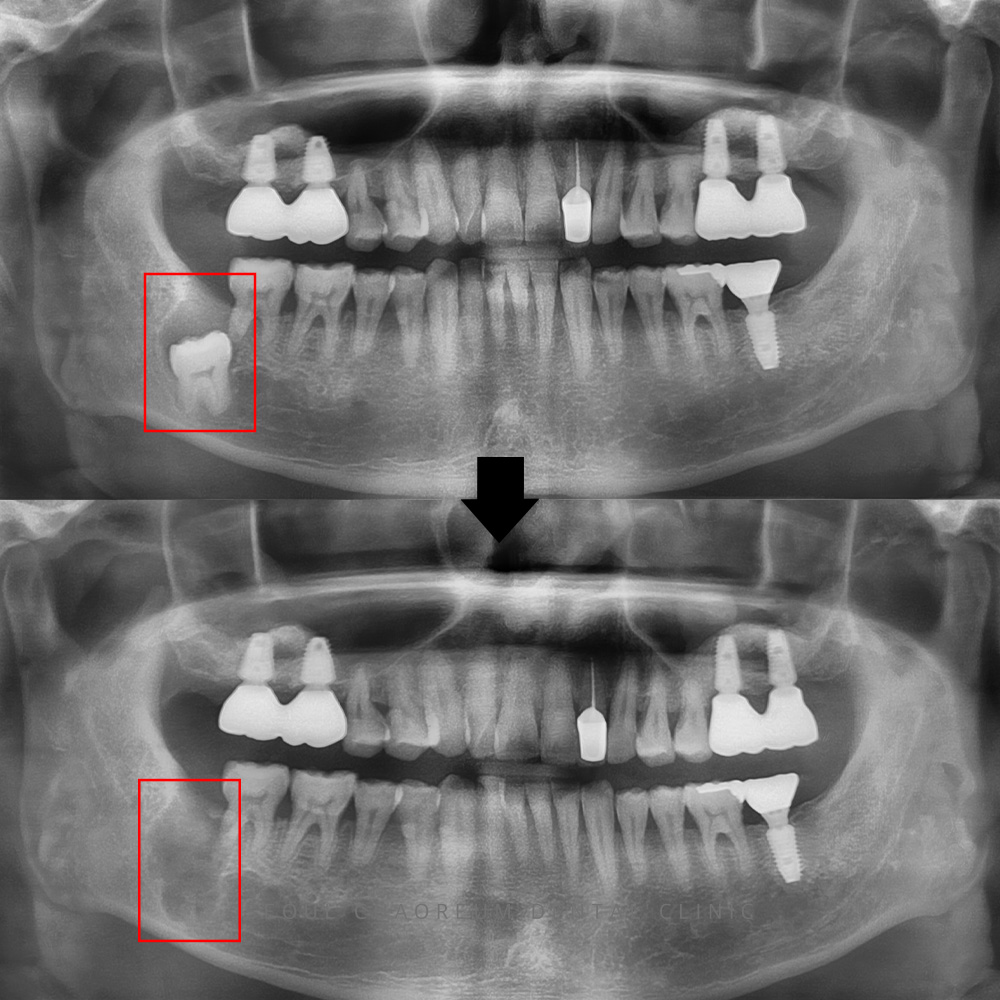

25.09.05 / 25.09.11

치료 전후 사진입니다.

환자분께서는 사랑니가 잇몸 안쪽 깊이

매복되어 있었기 때문에,

내부에 어떤 변화가 있는지

미처 알지 못하셨습니다.

하지만 정밀 촬영을 통해

성치성낭종을 조기에 발견하고

신속히 발치와 낭종 제거를 진행하여,

주변 치아에 추가적인 영향을

미리 막을 수 있었습니다.